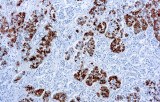

CE/IVD antibodies for immunohistochemistry (IHC) in neuropathology are validated in vitro diagnostic reagents used to detect specific neuronal and glial antigens in formalin-fixed paraffin-embedded (FFPE) tissue. Peer-reviewed neuropathology literature supports their role in improving reproducibility and diagnostic accuracy in central nervous system (CNS) diseases, including brain tumors and neurodegenerative disorders.

Targeted proteins such as GFAP, OLIG2, NeuN, synaptophysin, neurofilament, and Iba1 reflect astrocytic, oligodendroglial, neuronal, and microglial lineages. Their expression patterns are widely used in peer-reviewed studies to define CNS cell identity, differentiation state, and neuroinflammatory or degenerative processes.

CE/IVD IHC antibodies support CNS tumor classification (gliomas, embryonal tumors, metastases), assist in differential diagnosis, and help identify proteinopathies associated with Alzheimer’s disease and other neurodegenerative conditions. They are routinely used in biomarker panels for tumor grading and diagnostic stratification in neuro-oncology.